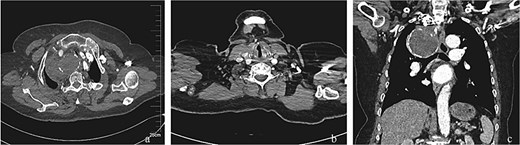

Postoperative management included daily aspirin (100 mg). The patient demonstrated no clinical evidence of distal limb ischemia or cerebrovascular events during the early postoperative period. At the 4-month postoperative follow-up, a surveillance thoracic aorta CTA performed at our institution confirmed complete aneurysm exclusion with satisfactory stent-graft apposition and absence of endoleak (Fig. 3). Longitudinal monitoring extended over 26 months revealed durable therapeutic efficacy. Importantly, the most recent telephone-based follow-up evaluation demonstrated persistent symptom remission, with no reported recurrence of chest pain, dyspneic episodes, or neurological deficits indicative of thromboembolic complications.

Post-interventional imaging surveillance at 4-month follow-up. (a) Axial CTA demonstrates complete thrombosis of the aneurysm sac following successful flow isolation, with volume reduction compared to pretreatment dimensions. (b) Sagittal reconstruction confirms absence of right vertebral artery opacification, consistent with deliberate ostial exclusion during the index procedure. (c) Coronal volume-rendered technique delineates organized thrombus within the collapsed aneurysm cavity, patency of the stent-graft lumen, and preserved distal subclavian artery perfusion through collateral channels. The radiopaque coil mass at the outflow tract confirms successful embolization endpoint achievement.